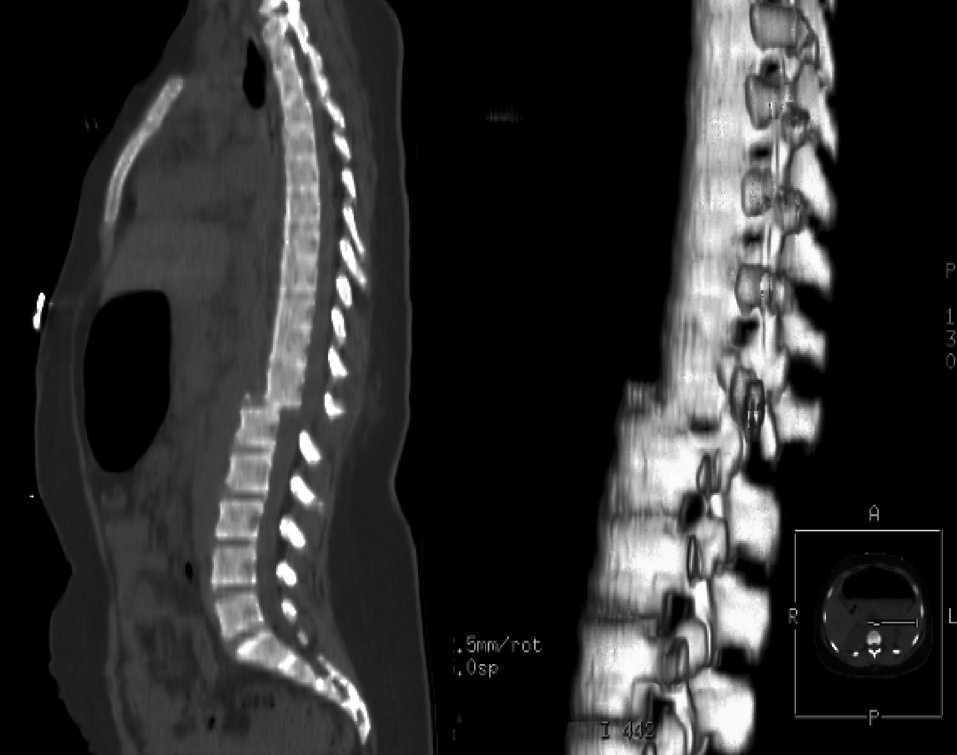

La descompresión quirúrgica dentro de las 24 horas posteriores a la lesión medular aguda se asocia con una mejor recuperación sensoriomotora. The Lancet Neurology, 21 de diciembre de 2020.